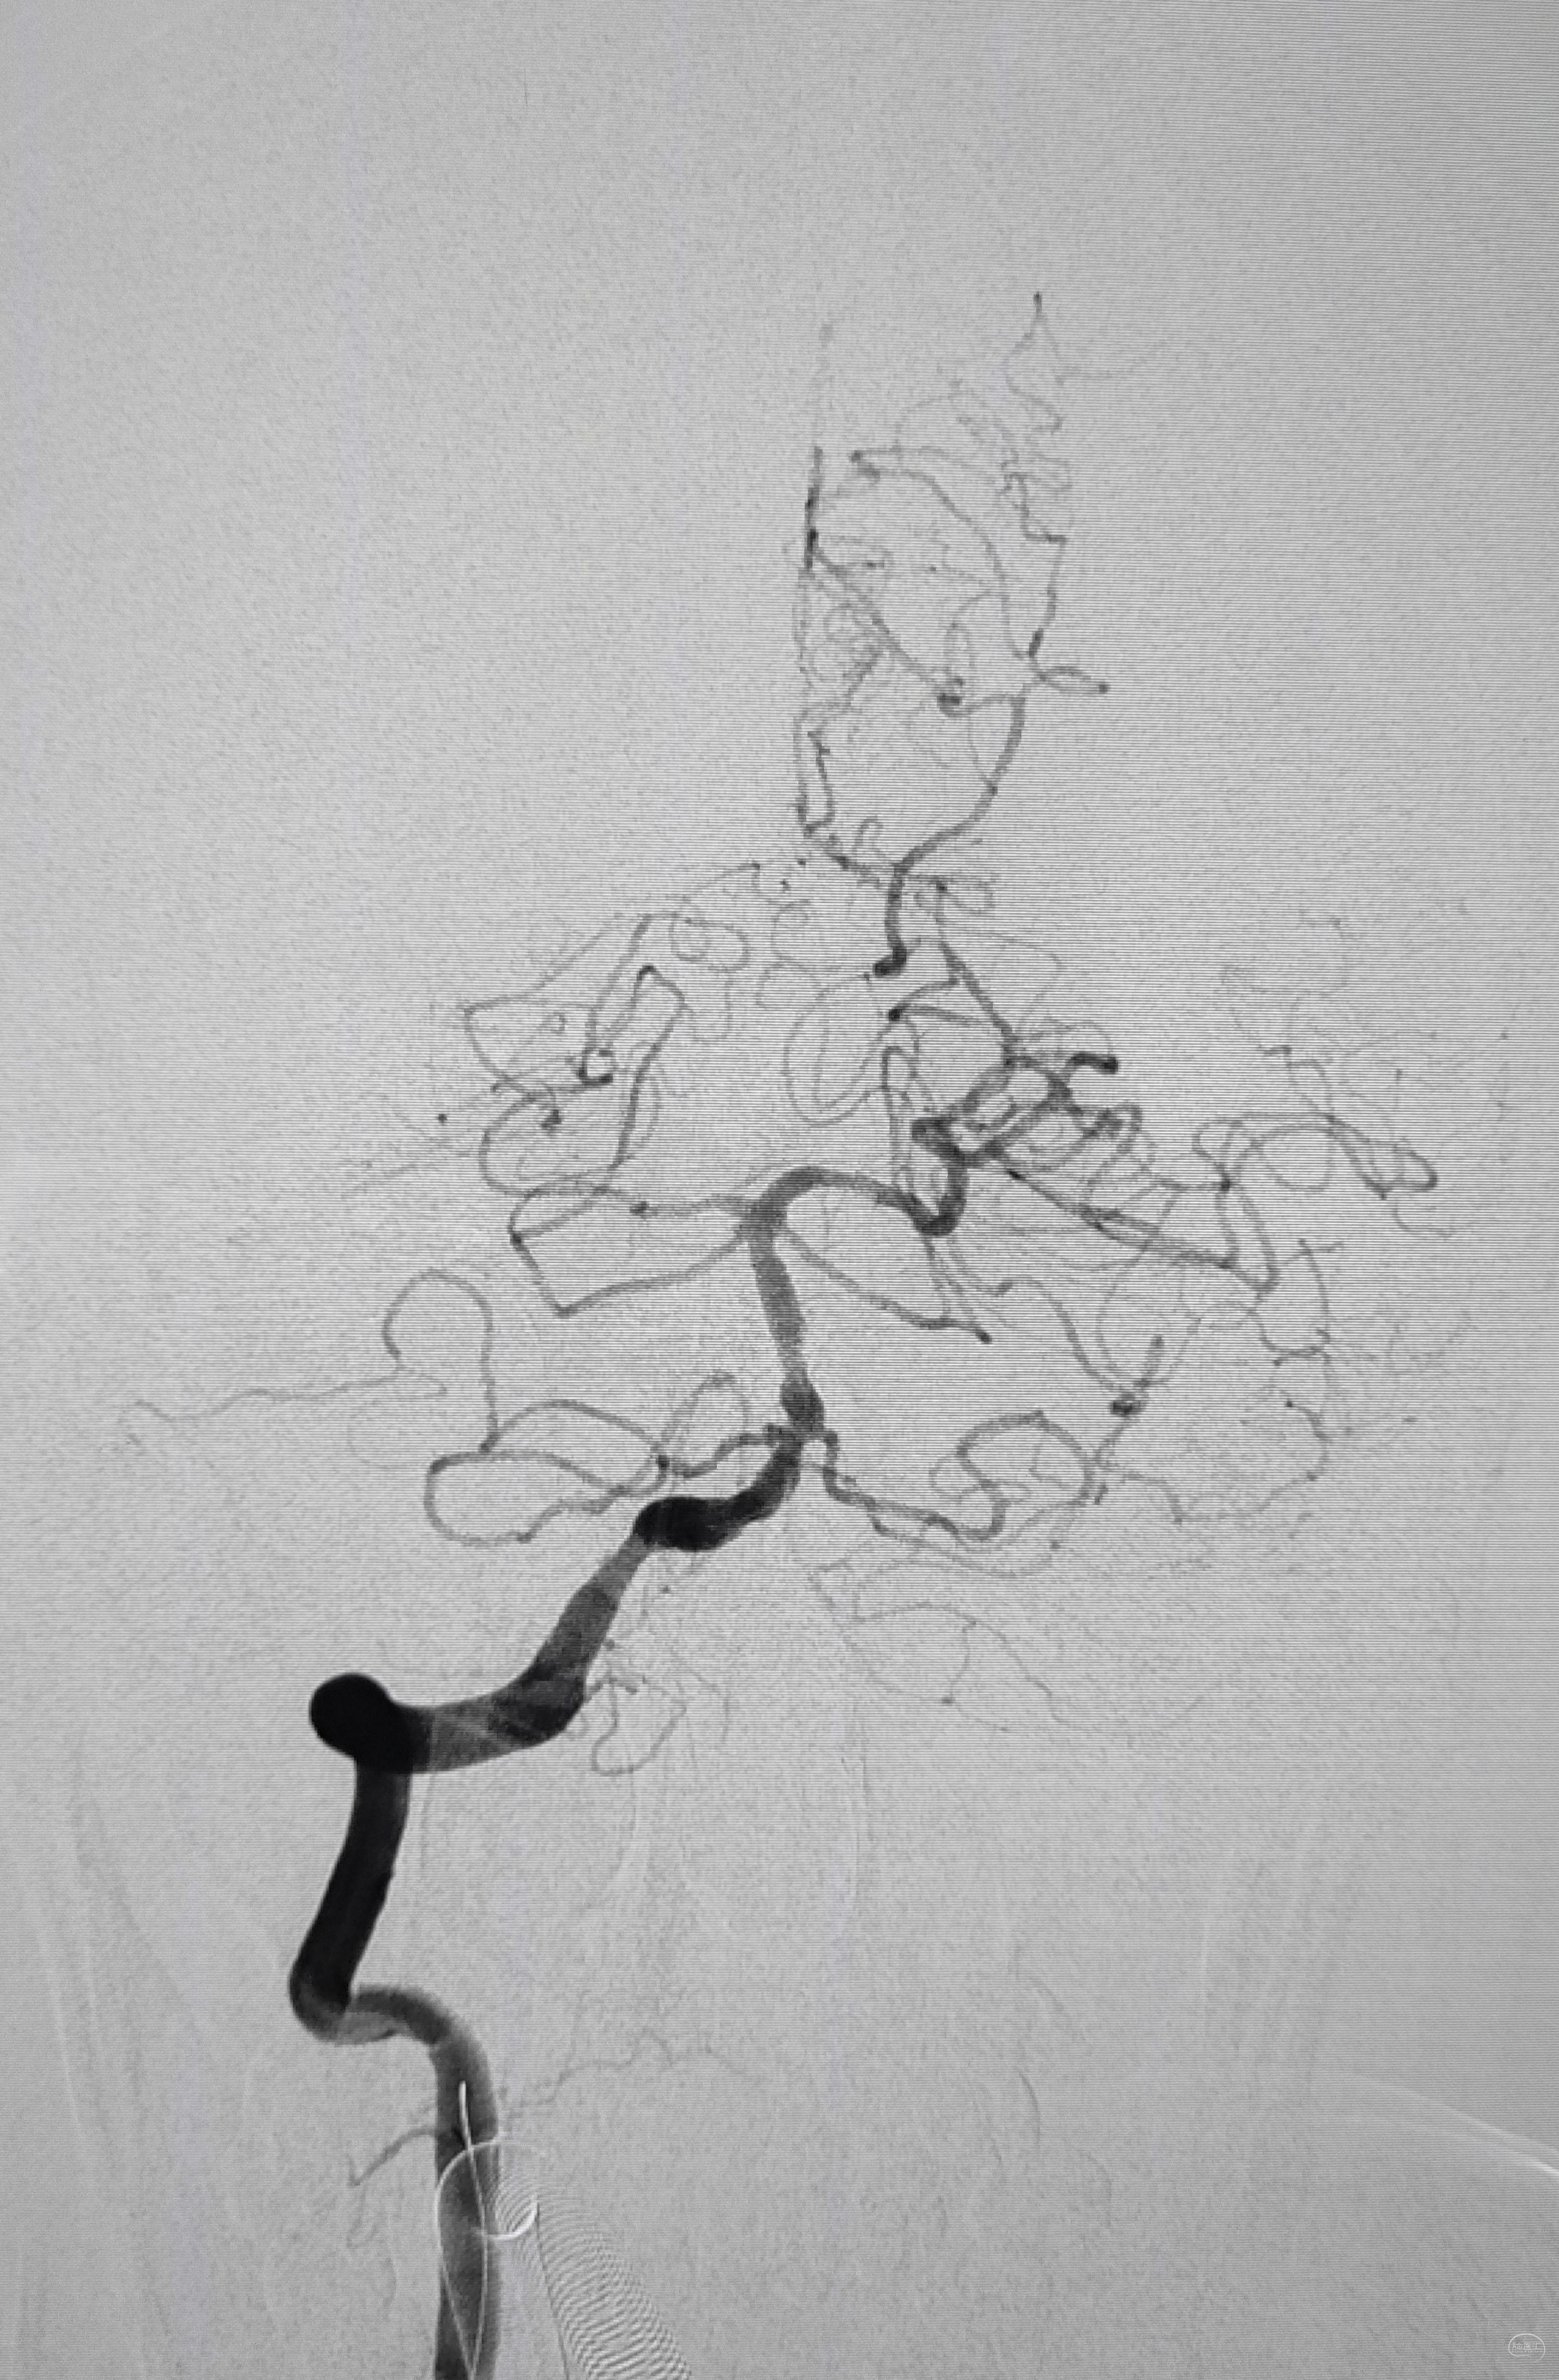

弓上造影初见:问题(一)左侧锁骨下动脉闭塞,主诉为头晕,双上肢收缩压差>20mmHg,这就是祸根?接着看弓上造影晚期像。

弓上造影晚期:剂量因素,逆流盗血隐隐可见,复合预期,那就看看对侧椎动脉情况吧